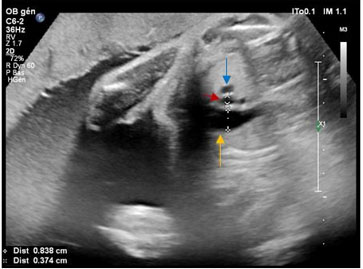

Ultrasound revealed a eutrophic fetus with an estimated fetal weight in the 48th percentile. At the cephalic pole, we observed a complete agenesis of the cerebellar vermis (Figure 1) without other associated brain abnormalities. The ear pavilion was anteverted, detached, and bulging (Figure 2).

Figure 1: Neurosonography showing cerebellum and complete agenesis of cerebellar vermis (A, B), measurement of cerebellum (A). The yellow arrow shows the cerebellar vermis agenesis with a communication between the 4th ventricle and the cisterna magna.

Posterior fossa cava malformations are most commons central nervous system abnormalities in isotretinoin fetopathy. Cerebellar vermis agenesia or hypoplasia and cerebellar hypoplasia are reported in 41.7% of isotretinoin fetopathy [1],[2],[4],[5]. In the present case a cerebellar vermis agenesia was noted. Moreover, hydrocephalus is reported in 37.5% cases.